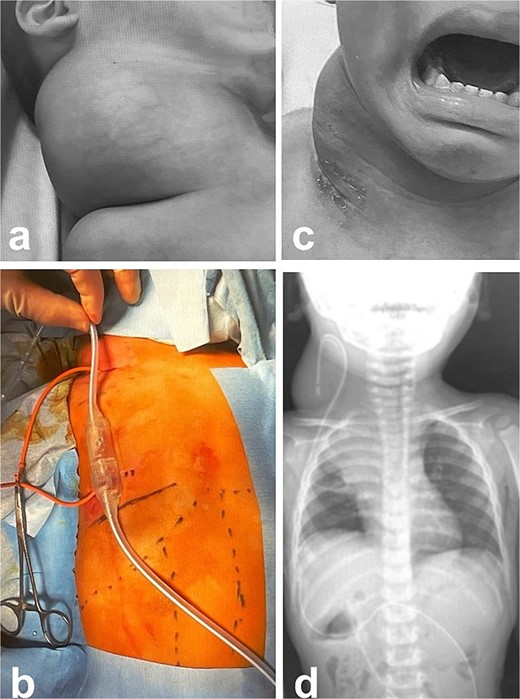

Intra- and post-operative findings from the first operation. (a) Intraoperative findings showed a huge bulge in the right neck. (b) A Denver shunt (peritoneovenous shunt) was inserted from the right cervical region to the abdominal cavity for volume reduction of the cervical cyst to prevent airway obstruction. Pump chamber with backflow prevention valve was implanted in the right anterior chest subcutaneous tissue. (c) Post-operative findings showed a reduction in the right neck swelling, even when crying. (d) The pressure on the trachea was shown to be relieved on the X-ray.